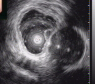

⑦超声胃镜

EUS是将微型高频超声探头安置在内镜前端,在内镜直视观察腔内形态的同时,又可进行实时超声扫描近距离探查,使靶器官的结构与图像更为清楚,为临床治疗方案的选择提供了有力的支持。我院消化内镜于2004年在四川省率先开展EUS新技术,目前拥有国内最新—代的EUS系统,它集超声内镜主机、高频小探头、三维超声探头、环扫内镜超声等 先进设备为—体。我院EUS诊疗组,现有教授1名、副教授2名,每年完成近千例消化道EUS诊疗,EUS诊疗技术达到省内先进水平。

为什么需要EUS

普通内镜检查只能发现消化道表面的病灶,通过EUS显示消化管壁层次结构及周围脏器病变,能更准确判断胃肠隆起病变的 性质、来源、肿瘤的浸润深度,还能取活检,指导确定治疗方案及判断疗效。

EUS适应症